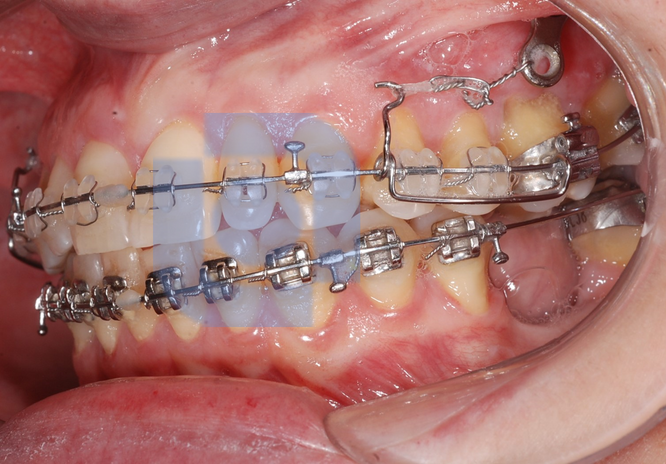

Cursor para Verticalização do molar

Distalização de Molar com Ancoragem Esquelética

Mini-Implante